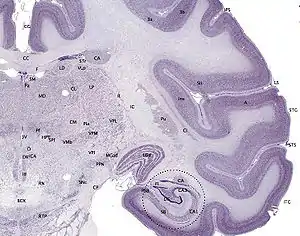

Medial surface of the human cerebral cortex Tissue slice from the brain of an adult macaque monkey. The cerebral cortex is depicted in dark violet.

Tissue slice from the brain of an adult macaque monkey. The cerebral cortex is depicted in dark violet.